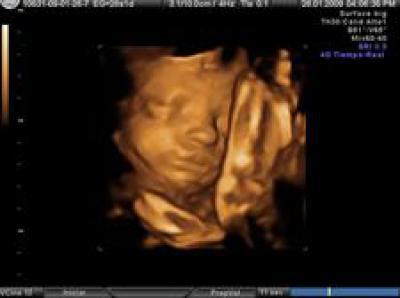

Los fetos bostezan en el útero

Mientras algunos expertos han sugerido que los fetos bostezan y otros afirman que es simplemente la apertura bucal, este estudio distingue claramente el bostezo, del no bostezo o la boca abierta, centrándose en la duración de la apertura de la boca.

Los investigadores analizaron las secuencias de vídeo 4D de 15 fetos sanos (ocho femeninos y siete masculinos) de entre 24 a 36 semanas de gestación para examinar de cerca todos los acontecimientos en un tramo de aftosa en el feto y hallaron que más de la mitad de las aberturas de la boca observadas fueron bostezos, según publica este miércoles la revista "Plos One". El bostezo se redujo desde las 28 semanas y que no hubo diferencias significativas entre niños y niñas en el bostezo frecuencia.

Aunque la función y la importancia del bostezo aún se desconoce, los hallazgos del estudio, financiado por el Consejo Económico y Social Research Council (ESRC), sugieren que el bostezo podría estar relacionada con el desarrollo del feto y como tal podría ser una indicación más para médico sobre la salud del bebé.

"Nuestro estudio longitudinal muestra que el bostezo disminuye al aumentar la edad fetal. A diferencia de nosotros, los fetos no bostezan por contagio ni por sueño, sino que la frecuencia de los bostezos en el útero puede estar relacionado con la maduración temprana del cerebro en la gestación", Nadja Reissland, del Departamento de la Universidad de Durham de Psicología.

Así, Reissland concretó que teniendo en cuenta que la frecuencia de bostezos en la muestra de fetos sanos se redujo desde las 28 semanas a 36 semanas de gestación, parece que el bostezo y la apertura bucal tener están relacionados con la maduración de la gestación, por ejemplo del sistema nervioso central.